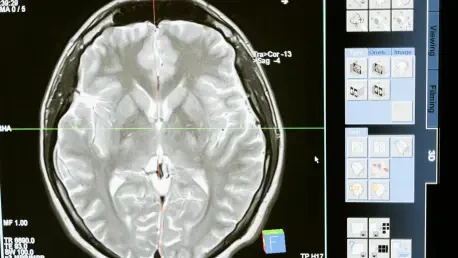

The convergence of artificial intelligence with medical imaging is fundamentally reshaping the landscape of oncological diagnostics, representing a quantum leap beyond incremental improvements in care. This technological fusion introduces an unprecedented level of precision and efficiency into the